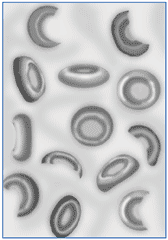

Гемолитическая анемия (лат. anaemia haemolytica от др.-греч. αἷμα «кровь» + λύσις «разрушение, растворение» + анемия) — групповое название редких заболеваний, общим признаком которых является усиленное разрушение эритроцитов, обусловливающее, с одной стороны, анемию и повышенное образование продуктов распада эритроцитов, с другой стороны — реактивно усиленный эритропоэз[1].